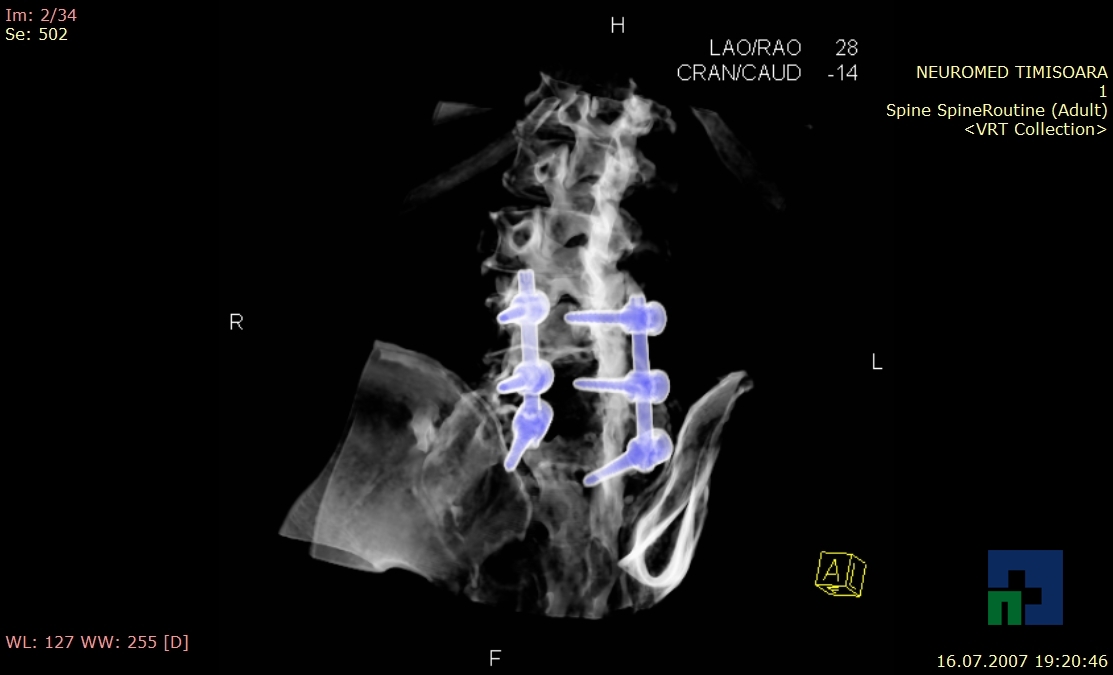

- Diagnosticul fracturilor:

- Unice

- Multiple

- Cu înfundare

- Complexe cranio-sinusale

- Complexe cranio-etmoidale

- Complexe cranio-orbitare

- Complexe cranio-faciale